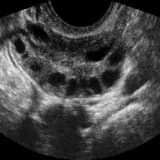

- **Antral folikül sayısı (AFC):** Ultrasonla yumurtalıkların antral folikül (gelişmeye aday yumurta) rezervine bakılır.